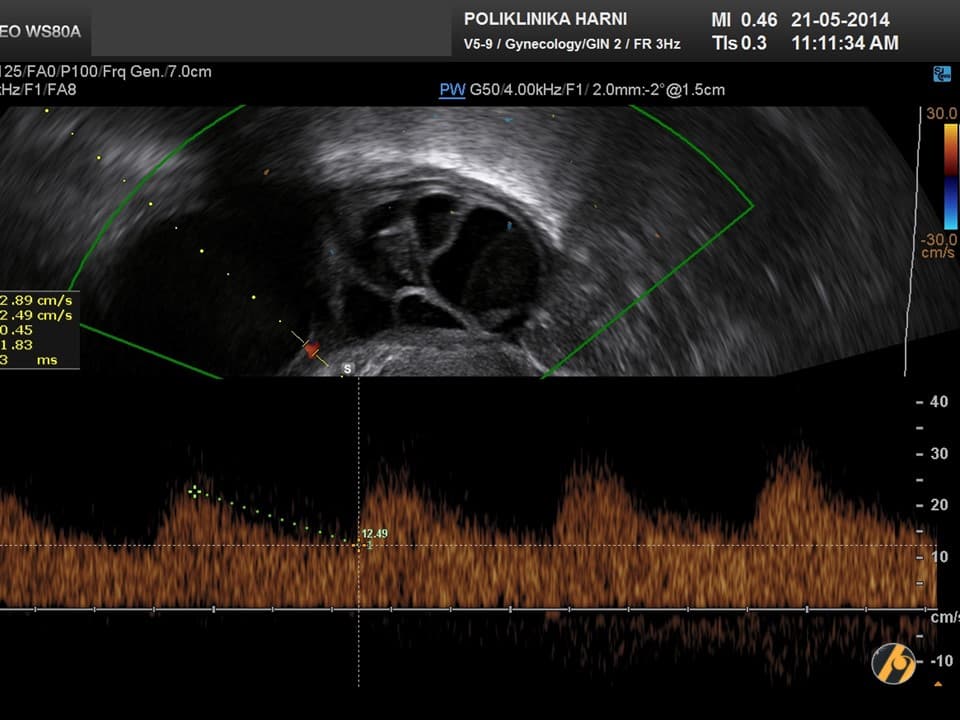

Nažalost, još uvijek ne postoji znanstveno potvrđena dijagnostička metoda koja bi se mogla nazvati metodom probira za karcinom jajnika. Za rano otkriće raka jajnika nužne su i veoma važne redovite ginekološke kontrole uz vaginalni ultrazvuk, odnosno pregled vaginalnim color-Doppler ultrazvukom. U slučaju nejasnih nalaza, uz standardnu laboratorijsku obradu određuju se tumorski biljezi. Optimalni tumorski biljeg za serozne karcinome koji se najčešće javljaju je CA 125, kod rjeđih mucinozni varijanti su to CEA i CA 19-9, a kod endometrioidnih i mucinoznih karcinoma AFP, te ß-hCG kod embrionalnih i koriokarcinoma. U novije vrijeme tumorskim biljezima za rak jajnika su pridodani HE-4 i ROMA indeks.